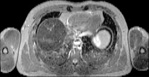

Visible Human male: Sectio transversalis 1477

CT

NMR

Pd                          / T2 \                         T1